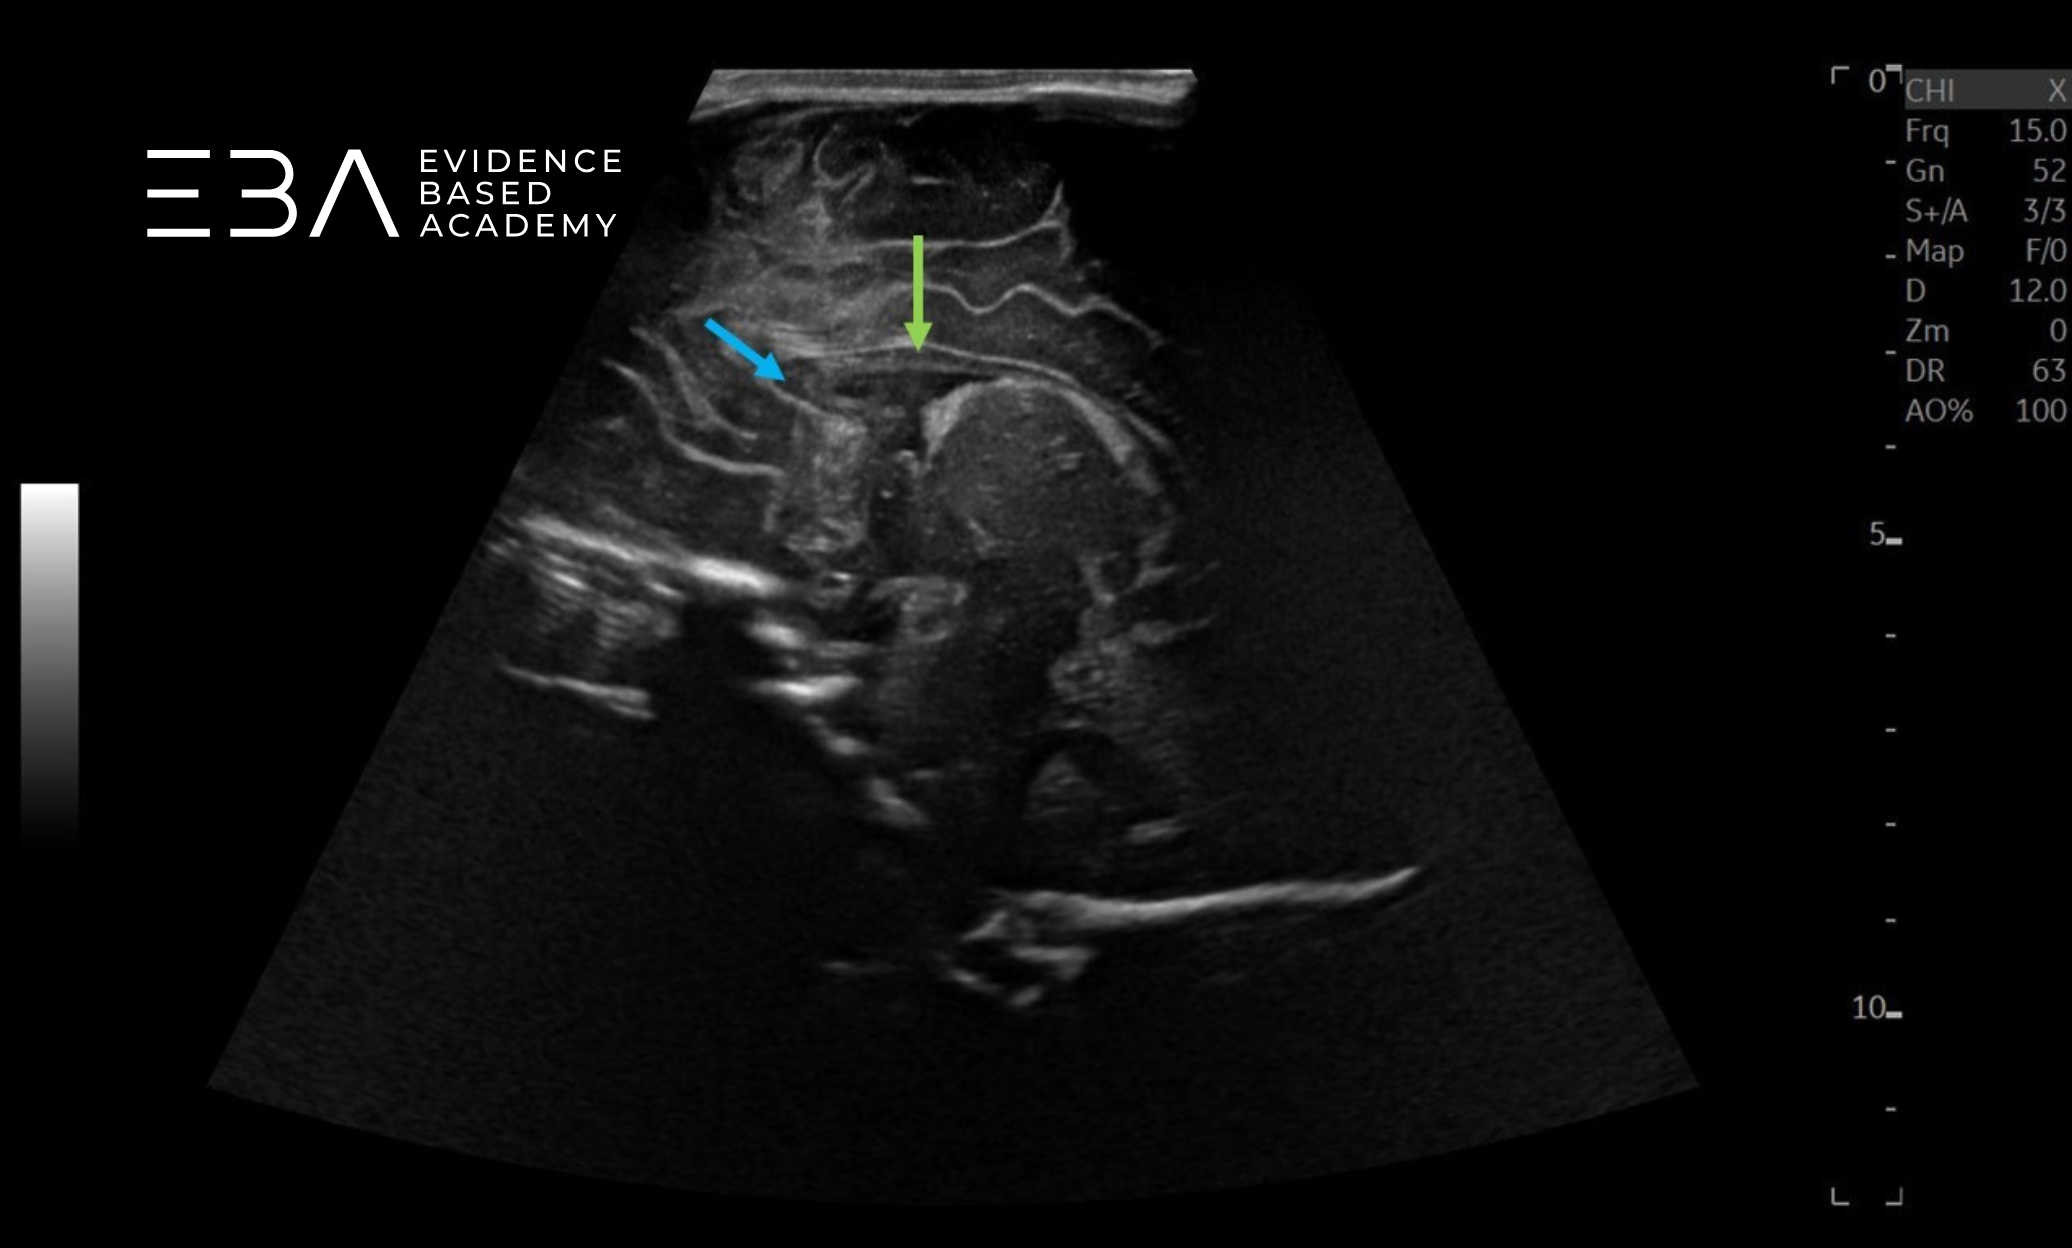

Badanie przez łuskę kości skroniowej, z głowicą umieszczoną poziomo powyżej i nieco przed uchem, umożliwia szczegółową ocenę pnia mózgu. Przez to okno możemy również uwidocznić komorę trzecią, wodociąg Sylwiusza i płaty skroniowe, a przy użyciu Dopplera – koło tętnicze Willisa (3). Jest to też dobre okno akustyczne do oceny tętnicy środkowej mózgu (2).

zdj. 5

Przyłożenie głowicy do projekcji strzałkowej przez łuskę kości skroniowej.

zdj. 5a

Głowica liniowa – badanie przez łuskę kości skroniowej. Konary mózgu (żółte strzałki), wodociąg mózgu (czerwona strzałka).